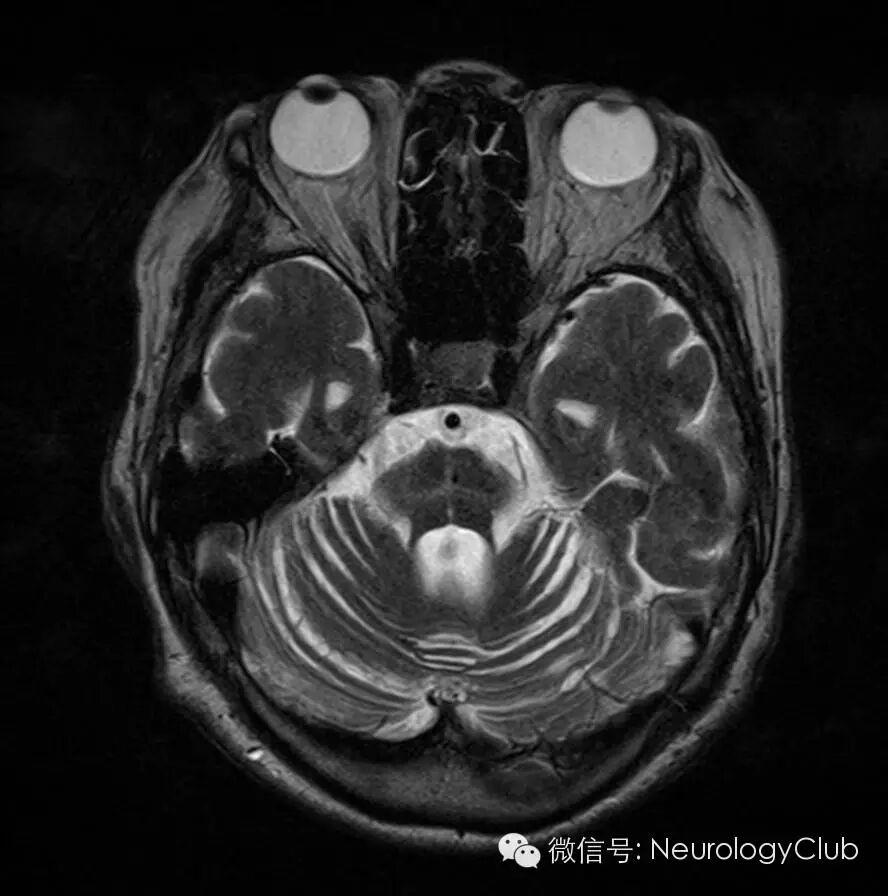

T2*WI诊断MSA的敏感度高于T2WI

近来的研究表明,梯度回波序列(T2*WI)比T2WI在发现MSA“十字征”和壳核改变上更为敏感。临床上怀疑MSA而普通MRI正常的患者,必要时可进一步行T2*WI检查。

A:MSA-P患者的T2WI上可见壳核外侧缘高信号(黑箭),而壳核内为低信号(白箭头)伴萎缩;B:T2*WI上有类似改变;C:另一MSA-P患者壳核在T2WI上无异常改变;D:同C患者T2*WI上可见壳核后外侧低信号;E-F:健康对照组T2WI和T2*WI上均未见壳核异常信号。